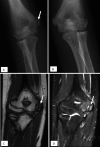

Figure 5.

14-year-old baseball pitcher with medial elbow pain for 1 month duration. (A) AP radiograph demonstrates asymmetric widening of the right medial epicondyle physis (arrow). (B) The left elbow, submitted for comparison, is unremarkable. (C,D) MRI performed the following day demonstrates edema within the medial condyle epiphysis (arrow) and the adjacent metaphysis of the humerus. The ulnar collateral ligament (not fully shown) was intact.